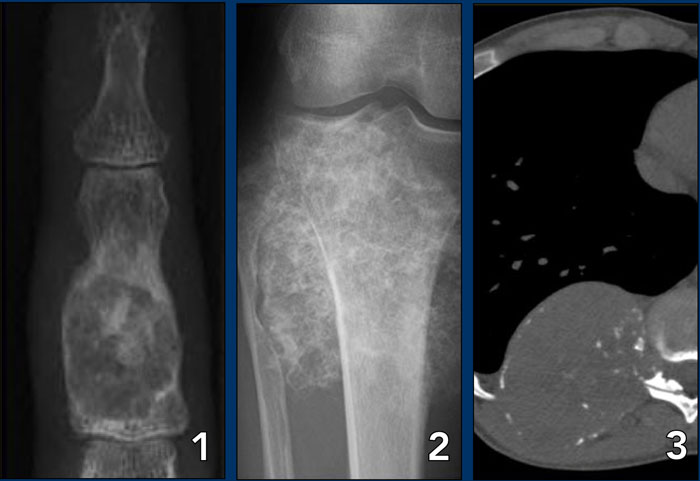

LEFT: Polyostotic Fibrous Dysplasia. RIGHT: Multiple osteolytic lesions in femurshaft LEFT: Polyostotic Fibrous Dysplasia. RIGHT: Multiple osteolytic lesions in femurshaft

Polyostotic or multiple lesions

Most bone tumors are solitary lesions.

If there are multiple or polyostotic lesions, the differential diagnosis must be adjusted.

Polyostotic lesions

NOF, fibrous dysplasia, multifocal osteomyelitis, enchondromas, osteochondoma, leukemia and metastatic Ewing' s sarcoma.

Multiple enchondromas are seen in Morbus Ollier.

Multiple enchondromas and hemangiomas are seen in Maffucci's syndrome.

Polyostotic lesions > 30 years

Common: Metastases, multiple myeloma, multiple enchondromas.

Less common: Fibrous dysplasia, Brown tumors of hyperparathyroidism, bone infarcts.

Mnemonic for multiple oseolytic lesions: FEEMHI:

Fibrous dysplasia, enchondromas, EG, Mets and myeloma, Hyperparathyroidism, Infection.